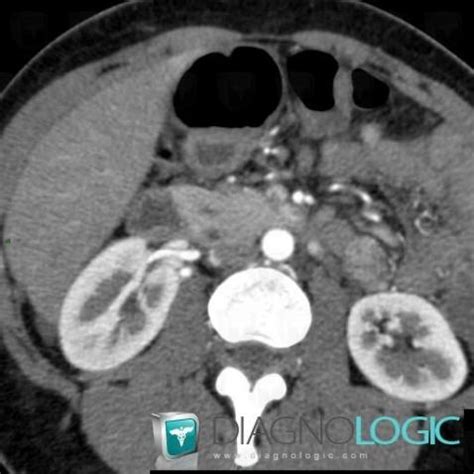

Radiology Case : Pancreas Divisum (CT) - Diagnologic

Source: legacy.diagnologic.com

.